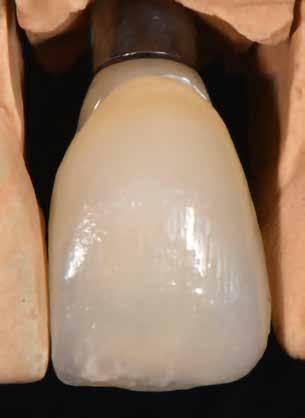

Implantátum-protetikai ellátás digitális tervezéssel

Egyetlen frontfog pótlása most is – akárcsak korábban – a királykategóriába tartozik. Bármely kis formai vagy színhiba kíméletlenül megmutatkozik minden mosolynál. Ezzel hihetetlen szintet nő, vagy csökken a páciens életminősége. Stefanie Flentje esetbemutatása ismerteti, hogyan valósíthatunk meg sikerrel implantátum elhorgonyzású borítókoronát a frontterületen.

A 64 éves hölgypáciens esztétikus pótlást kívánt 21-es foga helyén, amelyet balesetet követően 2022-ben távolítottak el. Az összes foga egészséges és vitális volt, így a 21-es régióba implantátum került, amelyre cirkónium-dioxid koronát terveztünk. Az implantátum típusát, pozícióját, átmérőjét egyedi anatómiai adottságainak és az adott helyviszonyoknak megfelelően választottuk meg.

építményhez gyári Camlog titánbázist használtunk, amit előzetesen befedtünk DCMhotbond fusio connect spray-vel. A titánbázis felületi kondicionálásához alkalmazott anyag kiváló, résmentes és tartós kötési alapot teremt a bázis és a rá készülő cirkon konstrukció között1. A cirkónium-dioxid egyedi felépítmény tervezését primer teleszkóp koronaként választottuk ki a CAD-szoftveres lehetőségek tárából. A felső mintát a beszórt titánbázissal ínymaszkkal és anélkül is beszkenneltük, akárcsak az antagonista mintát. A titánbázist hárompontos vonatkoztatással illesztettük a digitális mintába, majd megállapítottuk a behelyezési irányt és az illesztő paramétereket (7–13. képek).

Tervezés és kivitelezés a laboratóriumban

Az implantátumról készült lenyomat, valamint az alginát antagonista fertőtlenítése után szuperkemény gipszből az előírások szerint elkészültek a minták. A felső mintát a technikai implantátum körül levehető ínymaszkkal készítettük. SAM-arcív segítségével habituális okklúzióba helyeztük a mintákat. A felső mintát előkészítettük a digitális tervezéshez, enyhén megformáltuk az emergenciaprofilt, hogy tökéletes legyen a rózsa-fehér esztétika. A fogszínt – a pácienssel történt egyeztetést követően – dokumentáltuk.

A felépítmény megmunkálása

A felépítmény marását és szinterezését követően felpasszítom a titánbázisra, majd összeforrasztom a kettőt a gyártó előírásai szerint a DCMhotbond fusio 12-vel

800 C°-on 1. A DCMhotbond fusio 12 üvegszerű szilikátalapú kerámiaforrasztó. A titánbázis és a cirkonfelépítmény résmentes kötésére használjuk. A Connector spray ajánlása szerint a forrasztási hézag 0,15-0,3 mm közötti 2. A forrasztást követően a fölösleget lefújjuk kb. 1,5 bar nyomáson, az emergenciaprofilt pedig magas fényre polírozzuk. Most parallelométerben (inkább frézgépben – a ford.) 2°os gyémánttal csiszolom durvától a finom állapotig a fejet. Ügyelek rá, hogy a váll kb. 0,5-1 mm-rel az ínyszél alá kerüljön, így nem lesz látható az átmenet a végleges koronánál. A felépítményt pirossal beszínezem, ami kizárólag a vizuális azonosítást segíti, így minden felületet szükség szerint munkálhatok meg. Végül lecsapom az incizális élt (20–24. képek).

20–21. képek: A kimart felépítmény a mintán.

22–23. képek: A felépítményt pirosra színezem a vizuális kontroll érdekében, így minden szükséges korrekció elvégzése látható.

24. kép: A kész felépítmény a mintán.

25–26. képek: Most beolvastam a felépítményt, meghatároztam a preparációs határt és a behelyezési irányt, majd újra tükröztem és illesztettem az 11-es fogat.